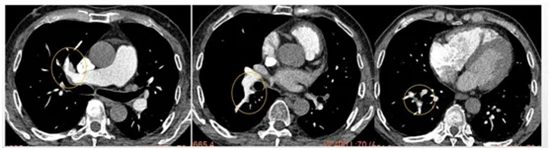

经肺动脉CTA检查,发现刘先生患上了大面积的“肺动脉栓塞”,情况危急,随即被收治入院。下肢静脉彩超进一步显示,其右腿深静脉血栓已蔓延至大腿根部。医疗团队迅速为他施行了“下腔静脉滤器植入术”,术后配合抗凝及溶栓治疗,刘先生的症状很快缓解。

▲ 经抗凝溶栓治疗后,肺动脉血栓基本消失